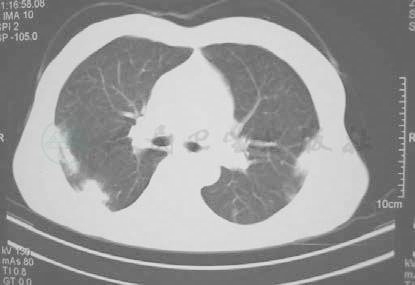

先后给予阿奇霉素、头孢呋辛等抗感染药物和氨茶碱等平喘药物治疗,体温一度降至正常,但咳嗽、咳痰、气喘症状未见缓解,后拟诊肺结核给予抗结核治疗,咳嗽、咳痰、气喘症状稍好转,但于抗结核3周后出现咳嗽加重,咳黄痰,痰中带血丝,6月15日复查胸部CT提示双肺靠近胸膜处多处斑片状渗出性病灶较前增多、增浓(图2),为进一步诊疗来我院。发病以来,精神、食欲和睡眠尚可,二便基本正常,体重无明显减轻。否认重大外伤、手术史,否认高血压、糖尿病等慢性病史,否认肝炎、结核病等传染病史,否认食物药物过敏史,无输血史。无外地长期居住史,无疫水接触史,家中养有鸽子,但未见有疫情,无烟酒嗜好,否认冶游史,月经婚育史、家族史无特殊。

图2-1 6月15日复查胸部CT示双肺靠近胸膜处多处斑片状渗出性病灶较前增多、增浓

图2-2 6月15日复查胸部CT示双肺靠近胸膜处多处斑片状渗出性病灶较前增多、增浓